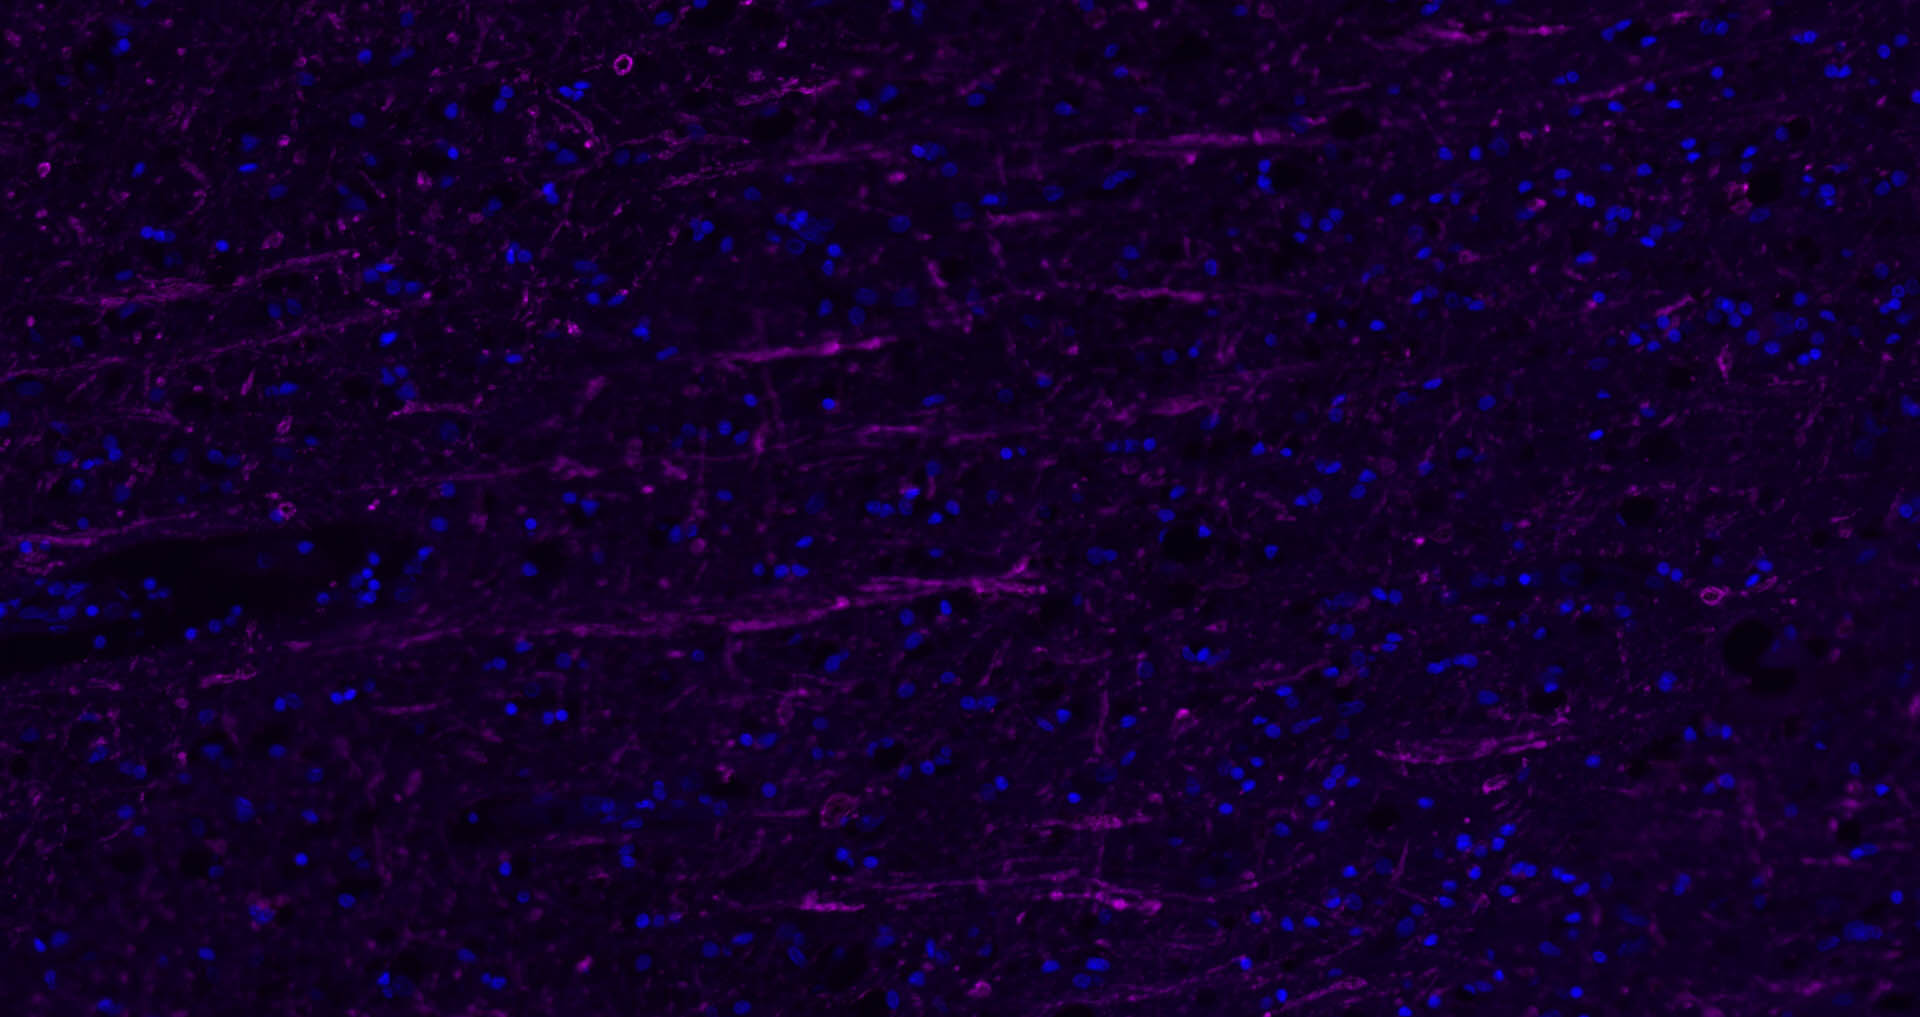

Paraformaldehyde-fixed, paraffin embedded Human Left Parietal Lobe; Antigen retrieval by boiling in sodium citrate buffer (pH6.0) for 15 min; Antibody incubation with MBP Polyclonal Antibody, Unconjugated (bs-0380R) at 1:200 overnight at 4°C. Followed by conjugated Goat Anti-Rabbit IgG antibody (Rose red, bs-0295D-Cy5), DAPI (blue, C02-04002) was used to stain the cell nuclei.

Paraformaldehyde-fixed, paraffin embedded Human Cerebellum; Antigen retrieval by boiling in sodium citrate buffer (pH6.0) for 15 min; Antibody incubation with MBP Polyclonal Antibody, Unconjugated (bs-0380R) at 1:200 overnight at 4°C. Followed by conjugated Goat Anti-Rabbit IgG antibody (Rose red, bs-0295D-Cy5), DAPI (blue, C02-04002) was used to stain the cell nuclei.

Paraformaldehyde-fixed, paraffin embedded Rat Cerebellum; Antigen retrieval by boiling in sodium citrate buffer (pH6.0) for 15 min; Antibody incubation with MBP Polyclonal Antibody, Unconjugated (bs-0380R) at 1:200 overnight at 4°C. Followed by conjugated Goat Anti-Rabbit IgG antibody (Rose red, bs-0295D-Cy5), DAPI (blue, C02-04002) was used to stain the cell nuclei.

Paraformaldehyde-fixed, paraffin embedded Mouse Cerebellum; Antigen retrieval by boiling in sodium citrate buffer (pH6.0) for 15 min; Antibody incubation with MBP Polyclonal Antibody, Unconjugated (bs-0380R) at 1:200 overnight at 4°C. Followed by conjugated Goat Anti-Rabbit IgG antibody (Rose red, bs-0295D-Cy5), DAPI (blue, C02-04002) was used to stain the cell nuclei.

Paraformaldehyde-fixed, paraffin embedded Mouse Cerebrum; Antigen retrieval by boiling in sodium citrate buffer (pH6.0) for 15 min; Antibody incubation with MBP Polyclonal Antibody, Unconjugated (bs-0380R) at 1:200 overnight at 4°C. Followed by conjugated Goat Anti-Rabbit IgG antibody (Rose red, bs-0295D-Cy5), DAPI (blue, C02-04002) was used to stain the cell nuclei.